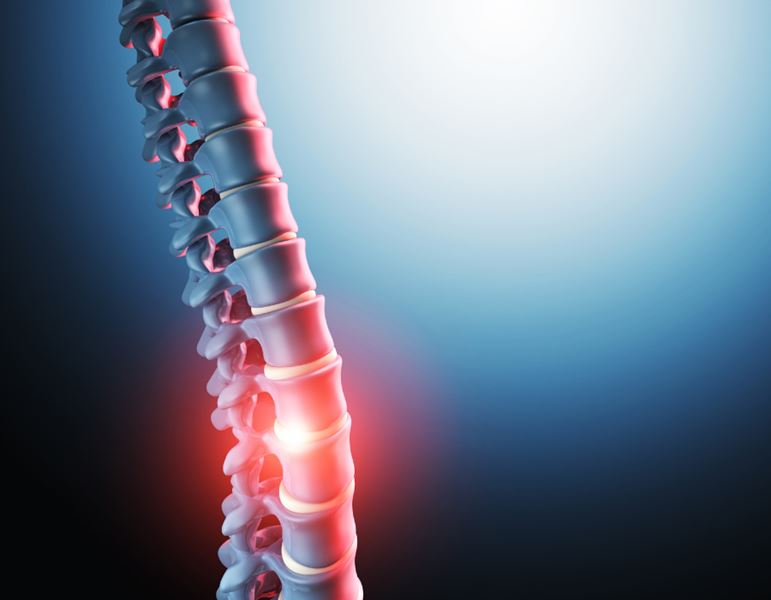

למידע נוסף על טיפול אלקטרומגנטי לסיאטיקה לחצו !

למידע נוסף על טיפול אלקטרומגנטי לבלט דיסק לחצו !

למידע נוסף על טיפול אלקטרומגנטי לפריצת דיסק לחצו !